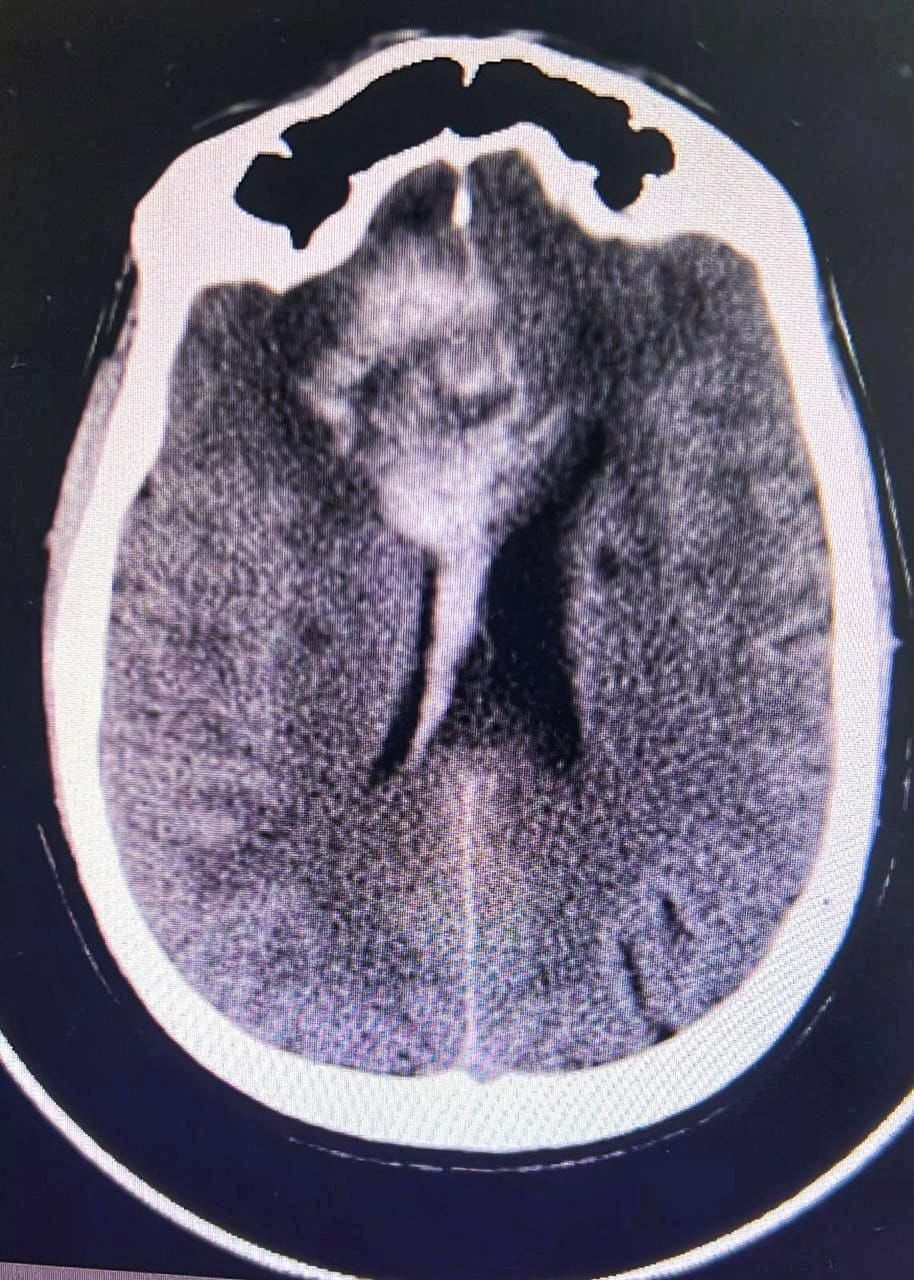

وتم اجراء الفحوصات اللازمة له وتبين وجود تمدد في الأوعية الدموية في الفص الأيسر من الدماغ مسببا انفجار الشريان الوسطي الدماغي الأيسر  .

وأوضح الدكتور أنور الهاشم رئيس قسم جراحة المخ والأعصاب والعمود الفقري ان الفحوصات أظهرت تلفا في مركز الحركة في الفص الأيسر ونقصا في التروية الدموية مهددا بفقدان وظائف هذا الفص بشكل شبه دائم .

مشيرا انه وبعد تقييم الحالة قرر الفريق الطبي اللجوء إلى تقنية إغلاق النزيف بالقسطرة لإعادة فتح التروية الدموية  وذلك بواسطة فريق الأشعة التداخلية حيث تم الدخول عبر شريان الفخذ وتوجيه القسطرة إلى الأوعية المصابة باستخدام تقنية مزدوجة لاغلاق النزيف بدعامة معدنية .